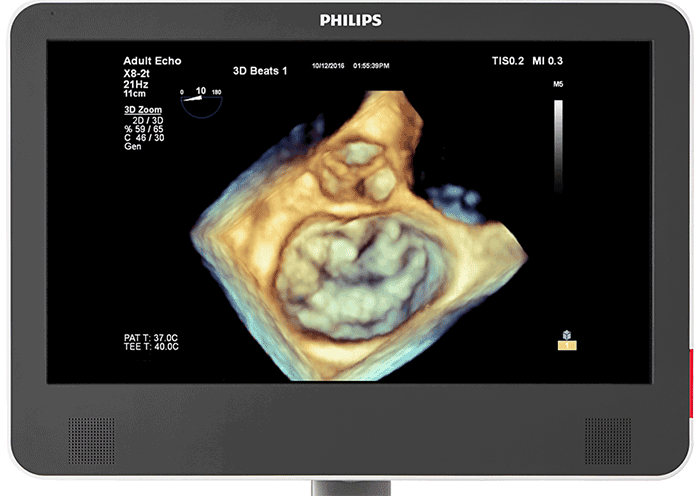

仮想光源によるフォトリアリスティックな3D画像 心臓組織用 TrueVue と仮想光源により、欠損部位や構造の奥行きの把握が容易になり、経胸腔の心臓組織および経食道エコーの視覚化も向上します。新型 EPIQ CVx Transcend を見た臨床医の 90%⁵が、新しい TrueVue 3D フォトリアリスティックレンダリングにより組織構造がより理解しやすく表示されるため、臨床的確信を強く持つことができると回答しました。

次世代 Live 3D TEE 用の設計 X8-2t Live 3D 経食道トランスジューサの音響設計では、より高い周波数と広い帯域幅により、2D および Live 3D での分解能が上がり、心筋組織の詳細が表現されるようになりました。その結果、Live 3D および Live 3D カラーにおいて、画質を犠牲にすることなく、真の意味でのワンビート画像取得とフィリップス史上最高のボリュームレートが実現しました。ハンドルには、リアルタイムで設定可能なファンクションボタンが搭載され、検査中でも追加機能を使用できます。